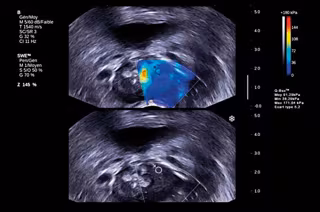

Desarrollan un nuevo método diagnóstico del cáncer a partir de la elasticidad de los tumores

Elastografia

Científicos del Hospital Universitario de Oslo (Noruega) han probado con éxito una nueva técnica que permite detectar el cáncer midiendo la elasticidad de los tumores que en los próximos años pueden convertirse en un método de diagnóstico tan determinante como ya lo son las mamografías o la resonancias magnéticas.

Según ha explicado uno de los autores de este trabajo, el radiólogo Per Kristian Hol, esta técnica llamada 'elastografía' puede ser "especialmente adecuada" para determinar la gravedad de la enfermedad.

En su estudio, comprobaron que los tumores no tienen la misma elasticidad que el tejido sano y que esta está relacionada con la densidad de los vasos sanguíneos, ya que los tumores tienen más vasos sanguíneos que el tejido sano y, de hecho, hay tumores malignos que suelen tener incluso más vasos sanguíneos y un mayor flujo de sangre que los tumores benignos.

"Los tumores tienen una elasticidad diferente, y hay tumores que pueden ser más o menos elásticos que el tejido sano. Además, hay algunos tumores que pueden diseminarse, mientras que otros no lo hacen. En otras palabras, se puede obtener un mapa completamente nuevo de órganos y tumores mediante la medición de elasticidad", ha defendido Sverre Holm, informático que ha colaborado en su desarrollo.

Para medir esta variable, la prueba es muy simple, ya que el médico coloca en el lugar que se va a examinar un vibrador que tiene un pulso de hasta 200 oscilaciones por segundo.

La onda de presión pasa al órgano a través del vibrador, lo que permite a los médicos estudiar la elasticidad de las partes sanas y enfermas.

El dispositivo emite un ultrasonido tradicional que envía una señal que regresa como un eco. El problema es que "es imposible distinguir entre tumores malignos y benignos con ecografía normal", dice Holm a la revista 'Apollon'.

No obstante, durante el desarrollo de la técnica se ha observado que el ultrasonido crea dos tipos de ondas. El tipo más común es ondas de presión, que bajan en el tejido, mientras que las otras son creadas por la presión de la radiación de la ondas de presión y se emiten horizontalmente, y reciben el nombre de ondas de corte.

Mientras que las ondas de presión son las más afectadas por los fluidos, las ondas de corte capturar las características de la otra 30 por ciento del cuerpo que no consisten de agua. "Estudiamos cómo se comportan las ondas de corte en el tejido, para medir su viscosidad, atenuación y velocidad", dice Holm.